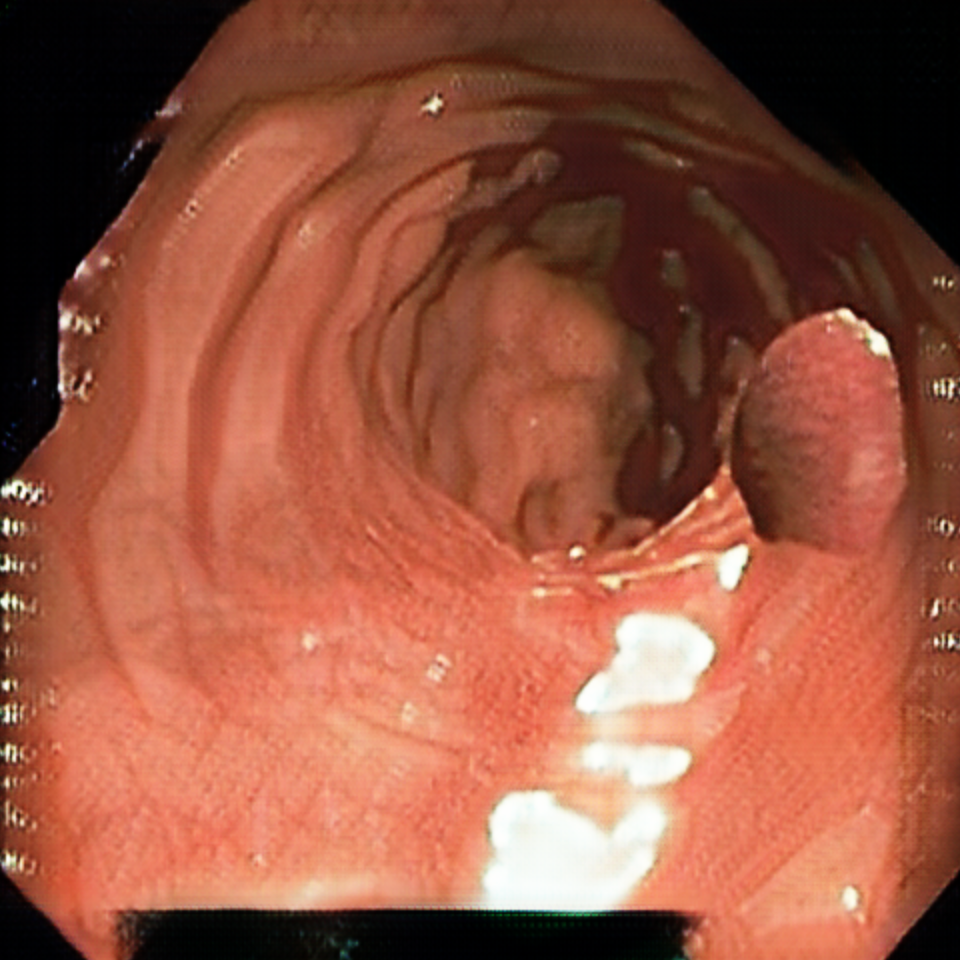

Early polyp segmentation was based in the texture and shape of the polyps. For example, Hwang et al. [8] used ellipse fitting techniques based on shape. However, some corectal polyps can be small (5mm) and are not detected by these techniques. In addition, the texture is easily confused with other tissues in the colon as can be seen in Figure 2.

With the rise of convolutional neural networks (CNNs) [10] the problem of the texture and shape of the polyps was solved and the accuracy was substantially increased. Several authors have applied deep convolutional networks to the polyp segmentation problem. Brandao et al. [2] proposed to use a fully convolutional neural network based on the VGG [16] architecture to identify and segment polyps. Unfortunately, the small datasets available and the large number of parameters make these large networks prone to overfitting. Zhou et al. [22] used an encoder-decoder network with dense skip pathways between layers that prevented the vanishing gradient problem of VGG networks. They also significantly reduced the number of parameters, reducing the amount of overfitting. More recently, Chao et al. [3] reduced the number of shortcut connections in the network to speed-up inference time, a critical issue when performing real-time colonoscopies in high-resolution. They focused on reducing the memory traffic to access intermediate features, reducing the latency. Finally, Huang et al. [7] improved the performance and inference time by combining HarDNet [3] with a cascaded partial decoder [21] that discards larger resolution features of shallower layers to reduce latency.